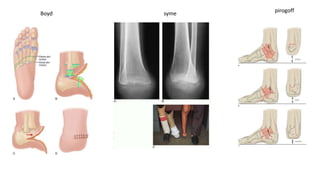

• BOYD Amputation:

• talectomy , excision of anterior part of calcaneus , forward shift of calcaneus and

calcaneotibial arthrodesis.

• PIROGOFF Amputation:

• Calcaneus is sectioned vertically, anterior part removed and its remaining posterior

part and heel flap are rotated forward and upward 90 degree until raw surface of

calcaneus meets denuded surface of distal end of tibia.

• Arthrodesis between tibia and part of calcaneus

Boyd

pirogoff

syme

• SYME Amputation:

• Bone transection at distal tibia and fibula 0.6 cm proximal to periphery of ankle joint

and passing through the dome of ankle centrally

• Tough durable skin of heel flap provides normal weight bearing

• Can be done in one stage or two stage